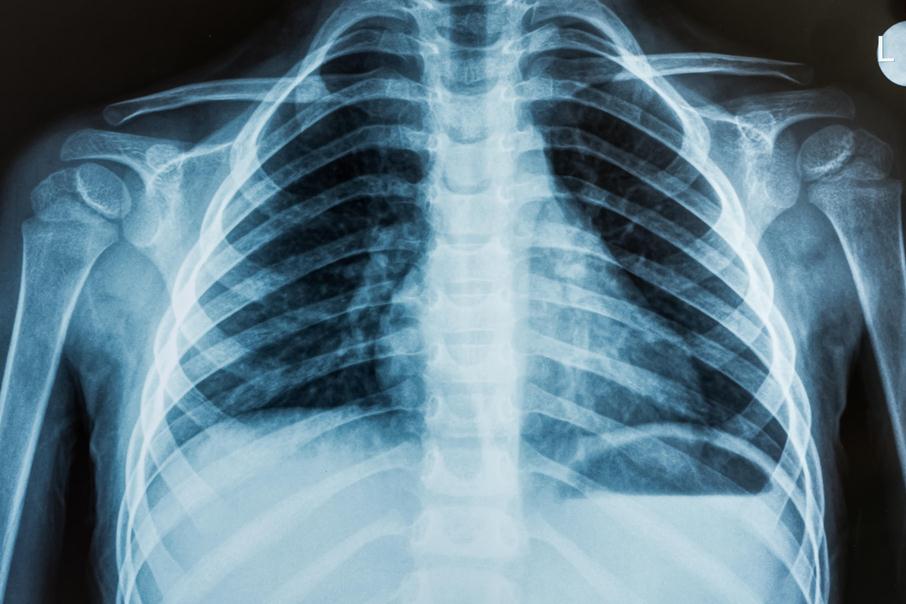

आजही आपण हाडांचे फ्रॅक्चर शोधण्यासाठी, क्षयाची बाधा समजण्यासाठी एक्स-रे छायाचित्र काढतो. एक्स-रे च्या मदतीने छायाचित्र काढले जाते तेव्हा हे किरण वेगवेगळ्या घनतेच्या पदार्थांना वेगळा प्रतिसाद देतात. हाडांसारखे घटक जास्त क्ष-किरण शोषतात. ते रेडिओग्राफ मध्ये पांढरे दिसतात. राखाडी किंवा काळसर भाग जो दिसतो तो उतींचा असतो. त्यात क्ष किरण अंशतः किंवा पूर्णपणे आरपार जातात. त्वचा, स्नायू किंवा पाण्याची घनता असलेले घटक यात भुरकट पांढऱ्या रंगात दिसतात.

छातीचा एक्स-रे काढताना पूर्ण श्वास घेऊन छाती फुगवण्यास सांगितले जाते. कारण त्यामुळे एक्स-रे आरपार जाऊन पुरेसे स्पष्ट छायाचित्र मिळते.